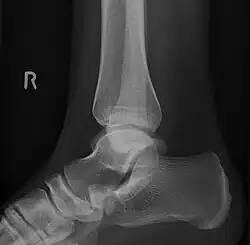

-

Lateral projection of type 2 -